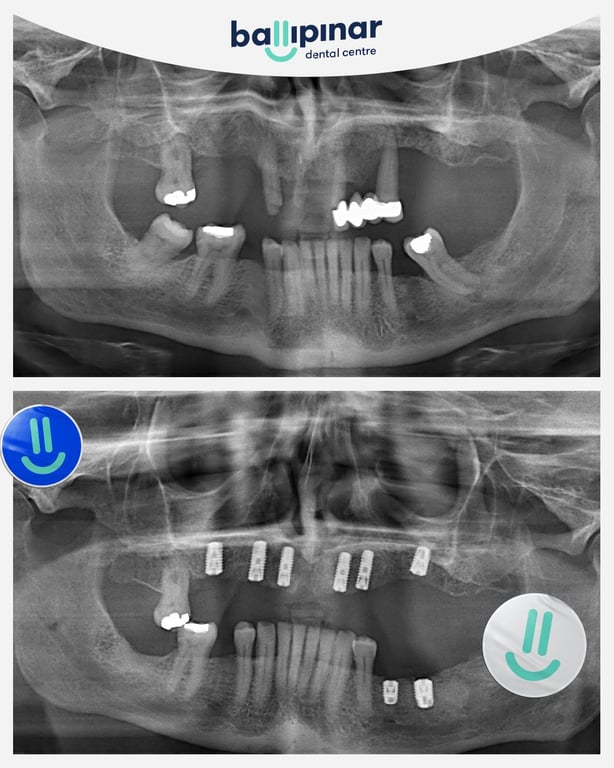

Dental implants Before & After

Explore all the before and after photos of dental implant procedures performed by Ballipinar in Turkey. Contact us today to achieve a beautiful smile.